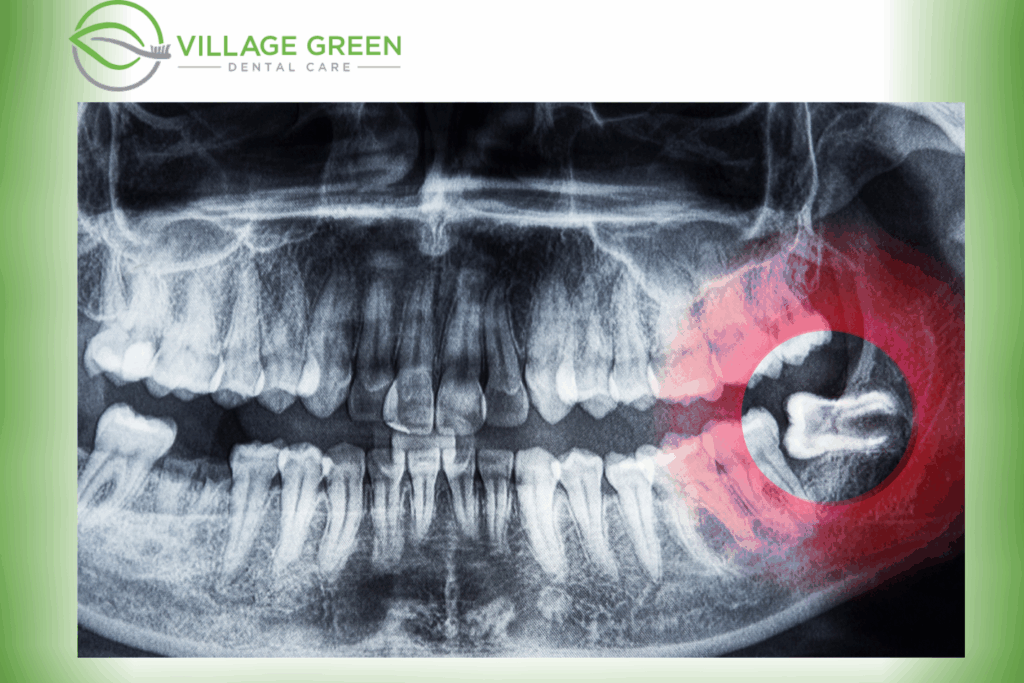

However, if they grow at an angle or stay trapped under the gums or jawbone, they can become

impacted wisdom teeth and often require removal.

Impacted wisdom teeth are one of the most common reasons for oral surgery. Studies suggest that a large percentage of people will have at least one impacted wisdom tooth in their lifetime,

which can increase the risk of pain, tooth decay, plaque build-up and infection.